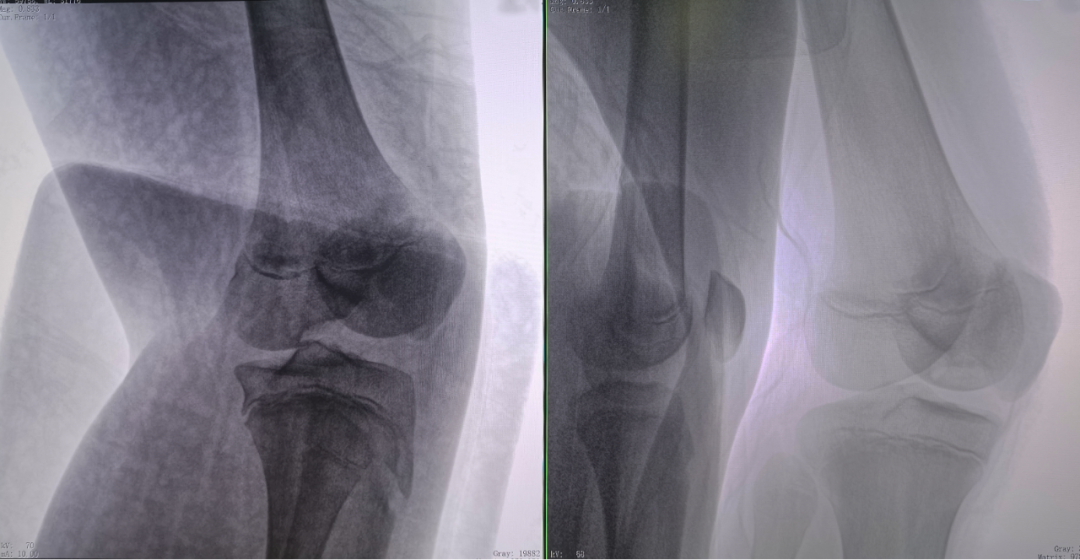

二維正側位影像

病例1:右側股骨遠端骨骺骨病(13歲)

二維影像看不到病灶點